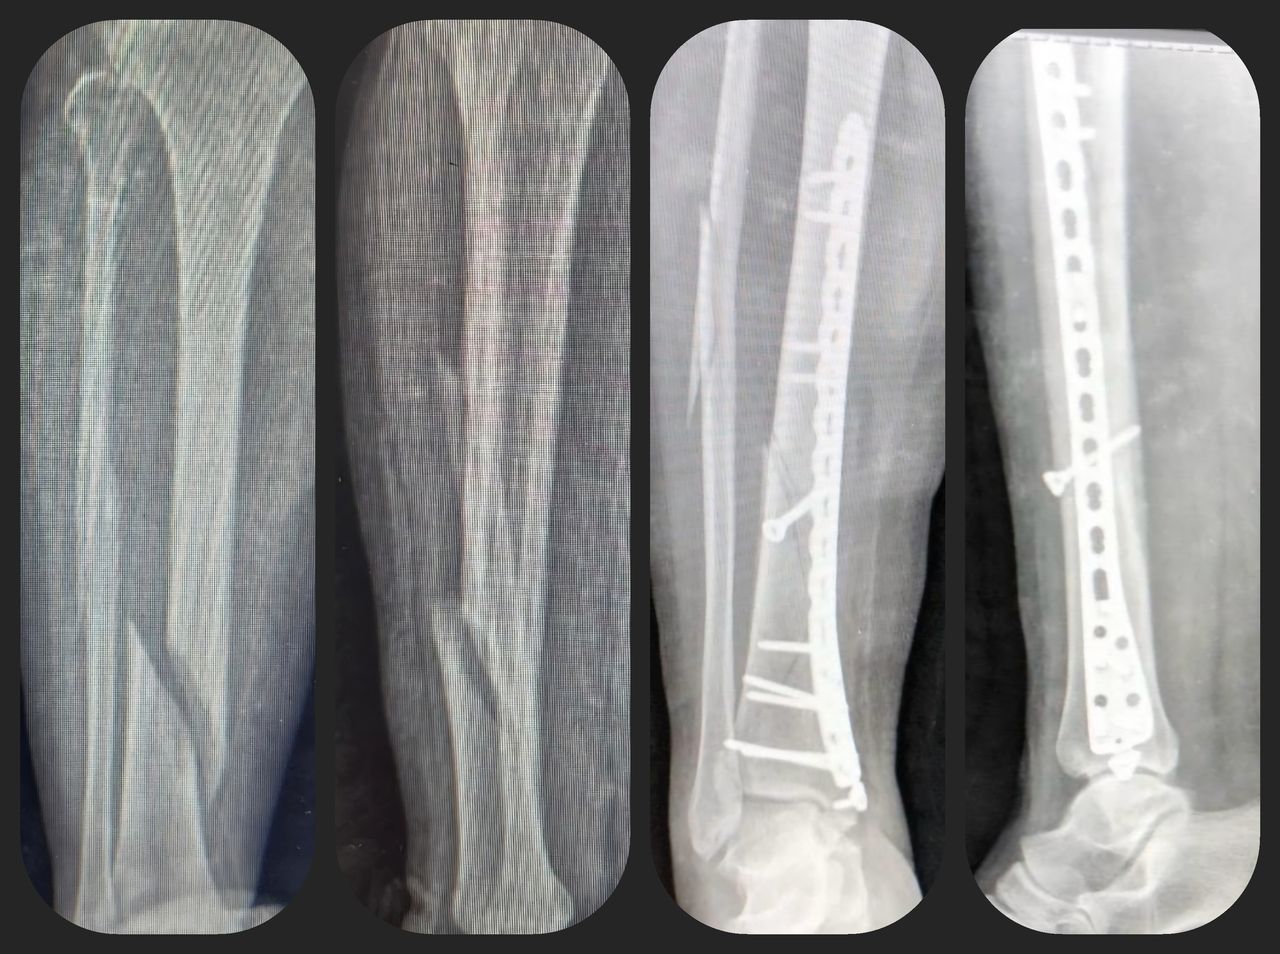

Fotos y videos